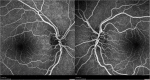

Case presentation: We present 3 particular presentations of LHON. Patient 1 was an 8-year-old boy admitted to the emergency department reporting a progressive bilateral visual loss and intermittent headaches. Neuro-ophthalmological examination revealed a bilateral pseudopapilledema. Lumbar puncture identified intracranial hypertension and the brain and orbits magnetic resonance imaging showed T2 hyperintensity in the posterior region of the left optic nerve and the optic chiasm. Patient 2 was a 12-year-old boy admitted to the emergency department reporting painless, progressive central vision loss in the right eye. Fundus examination revealed a hyperemic disc and vascular network papillary and peripapillary vascular microdilations. Three months later, the left eye presented visual loss. Patient 3 was a 6-year-old female child referred to the neuro-ophthalmology specialist due to painless central visual loss in both eyes. Her BCVA was 1/10 and counting fingers in right and left eye, respectively, and fundus examination revealed a pallor optic disc in the temporal sector.